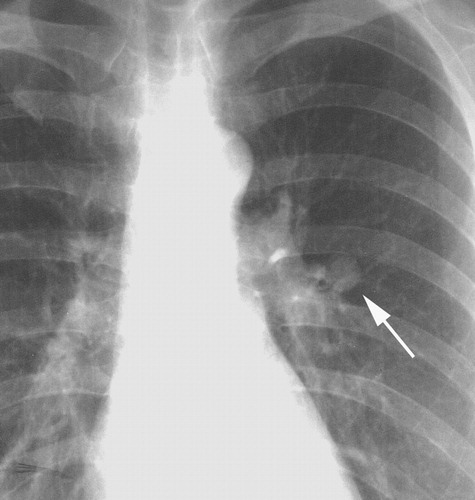

Pulmonary TB

Active pulmonary TB

Ghon complex on X-ray

Ghon complex on CXR

Pulmonary TB (active disease) Symptomatic pulmonary infection

• Primary TB: hilar lymphadenopathy, Ghon focus / Ghon complex.

• Post-primary (reactivation) TB: upper lobe/apical consolidations, cavitation, fibrosis, sometimes pleural effusions.